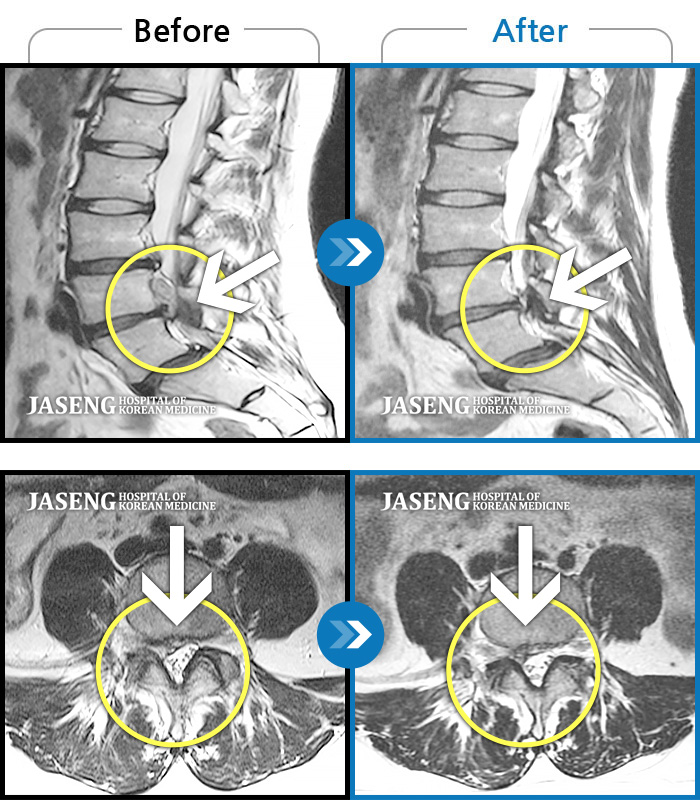

허리디스크

보라매 · 왕오호 원장

좌측 허리 통증 및 좌측 다리 저림

촬영시기

2016.05.21 ~ 2018.04.13